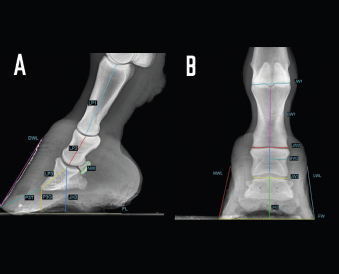

In addition, a total of 18 morphometric parameters were evaluated in 16 out of 56 forefeet for LM and DPa views (Fig. 2). A detailed description is given in Table 2.

Fig. 2. LM (A) and dorsopalmar (B) radiographs of a normal donkey foot to show the morphometric parameters established using Osirix DICOM Viewer (Pixmeo SARL, Switzerland). (A) Key: LP1, length of first phalanx. LP2. LP3. JH3, height of the distal interphalangeal joint. NW, width of the navicular bone. FL. DWL. P3T. P3G. Dorsal is to the left of image and palmar is to the right. (B) Key: JW1, JW2, JW3, BW1, BW2, and JH3. Dorsopalmar radiographic view. MWL, medial wall length, LWL, FW, width of the foot. Medial is to the left of image and lateral is to the right.